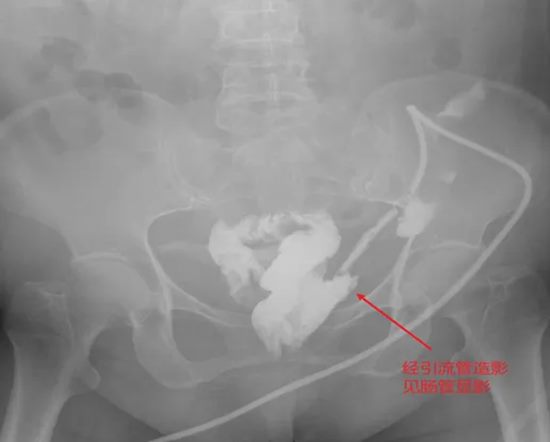

病情简述:患者胰十二指肠术后并发胆瘘、胰瘘、肠瘘,外院四次清创仍无法控制,瘘口位置不明。

诊疗破局:明确诊断是治疗的起点。团队通过精心设计的多次、多途径造影检查,最终精准定位瘘口位于结肠肝区。明确“敌情”后,先通过营养支持稳住“阵地”,再行回肠造口转流,为后续治疗创造了条件。